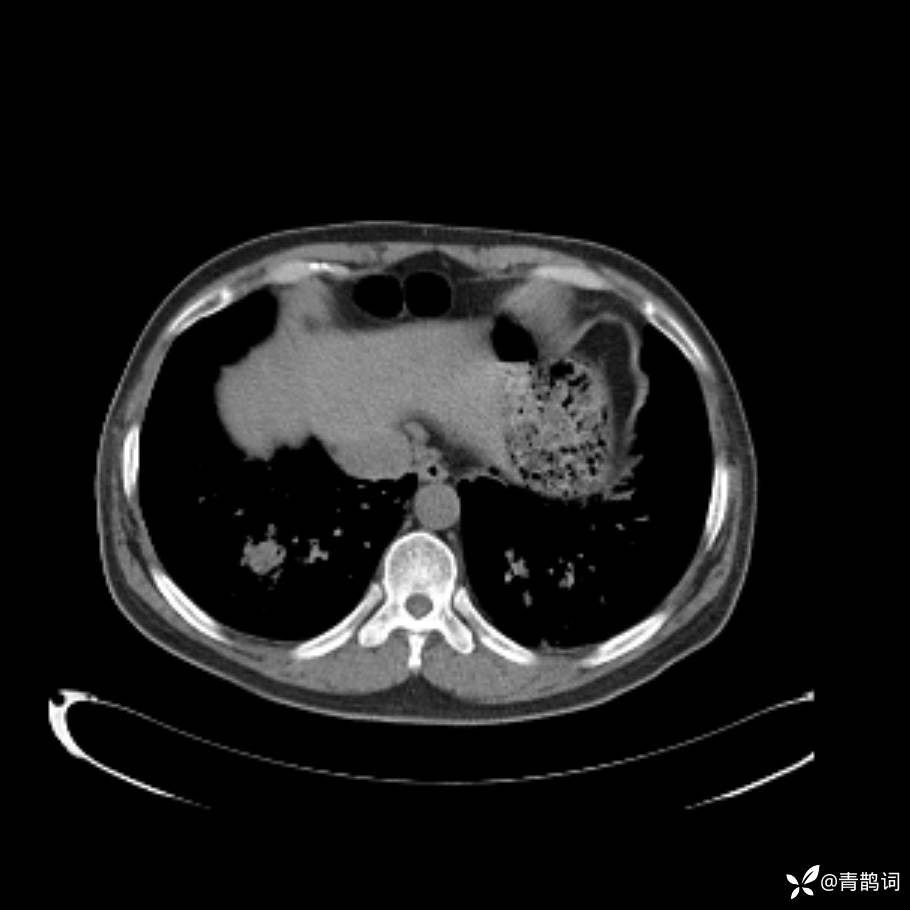

患者年龄:30岁。

患者性别:男。

简要病史:左颜面部肿胀2年,反复咳嗽咳痰,逐渐加重。

结合病史及影像学表现,期待评论区各位老师各抒己见~